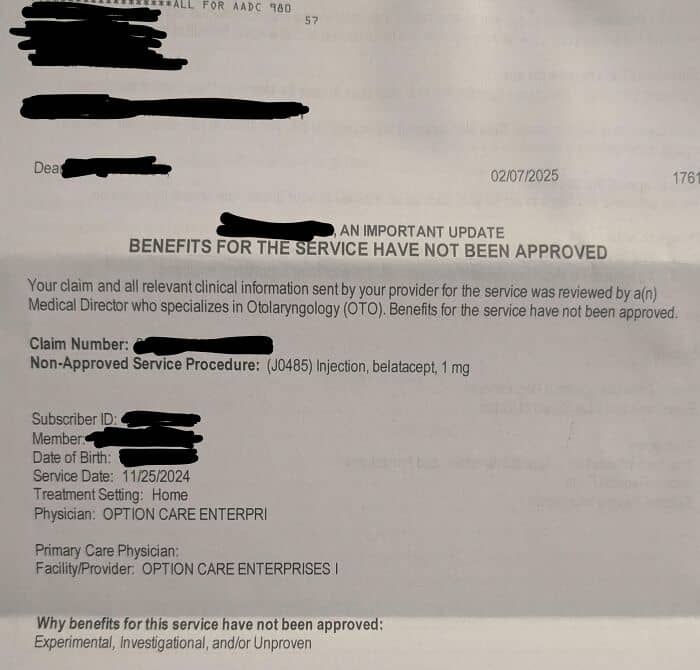

#52 American Insurance